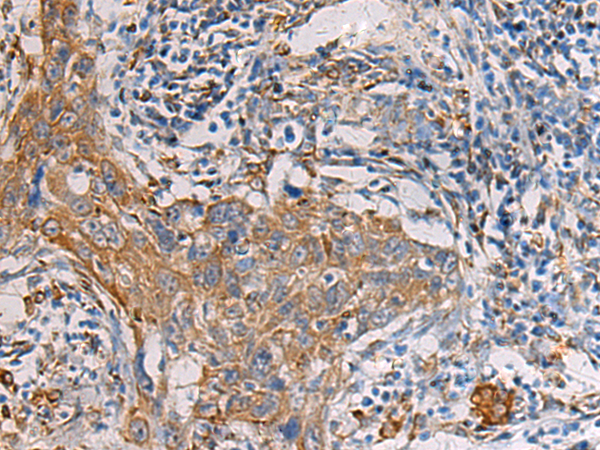

IHC (Immunohistochemisry)

(Immunohistochemistry of paraffin-embedded Human colorectal cancer tissue using PAIP1 Polyclonal Antibody at dilution of 1:60(×200))